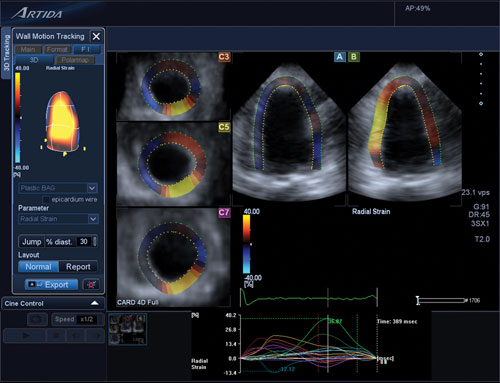

One cardiac ultrasound innovation that is widely used to assess cancer patients’ hearts is echo strain imaging. This advanced visualization software allows simultaneous assessment of three different views of the myocardium. The software allows quantification of the amount of left ventricular (LV) systolic function muscle strain in each view. Storozynsky said strain imaging can show microscopic changes in movement of the myocardium prior to the presentation of symptoms.